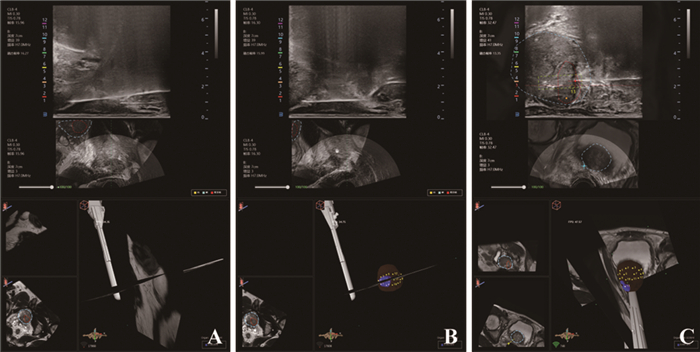

采用“一平面三点”双探头超声定位局部麻醉方式。“一平面”即在会阴局部涂抹复方利多卡因乳膏进行皮肤表面麻醉,联合穿刺进针区域注射盐酸利多卡因进行皮下浸润麻醉,以减轻活检针进入皮肤的疼痛感。将2%盐酸利多卡因注射液10.0 ml用等体积10.0 ml 0.9%氯化钠溶液进行1:1稀释。使用10 ml稀释后的利多卡因注射液对穿刺区域进行皮下浸润麻醉。“三点”即前列腺尖部、前列腺左右两侧面进针进行神经阻滞麻醉,最大程度阻滞前列腺周围神经,减轻活检针在前列腺内穿刺引起的疼痛感。抽取稀释后的利多卡因注射液10 ml,更换神经阻滞穿刺长针头(0.7×80 mm,浙江康德莱医疗器械股份有限公司),在超声引导下平行尿道垂直穿入前列腺尖部,进针沿途缓慢注射盐酸利多卡因,针尖至前列腺尖部包膜,在双平面超声引导下注射麻醉药可见包膜下低回声隆起,见图 1A。为避免麻醉药入血,每次注射前均回抽注射器确定无回血。同样的方法在前列腺左右两侧包膜下注射利多卡因注射液进行前列腺周围神经阻滞麻醉,见图 1B。麻醉成功后,将超声探头穿刺架固定在腔内双平面超声探头上并缓慢推入直肠内,在电磁针尖引导下由同一名经验丰富的高年资医师使用活检针行靶区病灶穿刺2~3针,再进行12针前列腺系统穿刺,见图 1C。穿刺结束后络合碘再次消毒会阴部,无菌纱布按压会阴穿刺区域2 min后局部加压包扎。

![]() 图 1 电磁针尖引导局麻经会阴前列腺多模态影像融合靶向穿刺术中超声图Figure 1 Ultrasound image of mpMRI-TRUS image fusion targeted transperineal prostate biopsy using electromagnetic needle tracking under local anesthesiaA: injection diagram of local anesthesia under the capsule at the tip of prostate; B: local anesthetic injection map under the capsule on the left and right sides of the prostate; C: mpMRI-TRUS image fusion targeted transperineal prostate biopsy; the red area is the target lesion, and the yellow rectangular frame area is the starting and end point of real-time monitoring of biopsy needle emission by using the electromagnetic navigation and tracking system.

图 1 电磁针尖引导局麻经会阴前列腺多模态影像融合靶向穿刺术中超声图Figure 1 Ultrasound image of mpMRI-TRUS image fusion targeted transperineal prostate biopsy using electromagnetic needle tracking under local anesthesiaA: injection diagram of local anesthesia under the capsule at the tip of prostate; B: local anesthetic injection map under the capsule on the left and right sides of the prostate; C: mpMRI-TRUS image fusion targeted transperineal prostate biopsy; the red area is the target lesion, and the yellow rectangular frame area is the starting and end point of real-time monitoring of biopsy needle emission by using the electromagnetic navigation and tracking system.1.3 观察指标